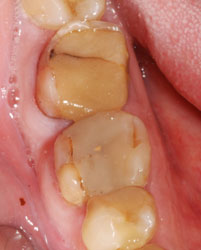

Такая же негерметичная пломба, такой же анкерный штифт… при этом твердые ткани сохранены гораздо лучше первого случая. По всему периметру зуба граница полости находится выше уровня десны, а, значит, по крайней мере, прогноз на долговечность реставрации будет вполне оптимистичным.

После удаления старой пломбы и анкерного штифта можно увидеть, что происходит внутри зуба под внешне вроде бы неплохой пломбой.